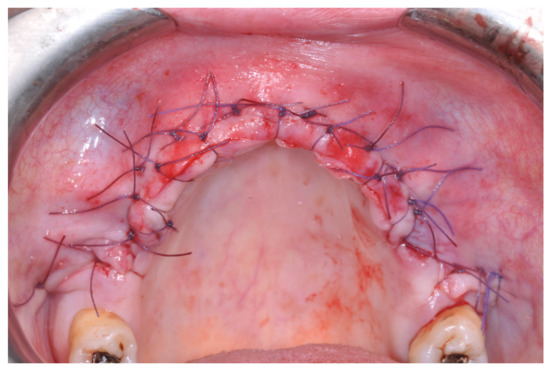

Resorbable sutures (Vicryl 6-0 SH1 needle of 17 mm 1/2c; Ethicon, New Brunswick, NJ, USA) were placed, alternating between single sutures and horizontal mattrass sutures (Figure 13).

Figure 13. After suturing.

2.3. Post-Operative Management